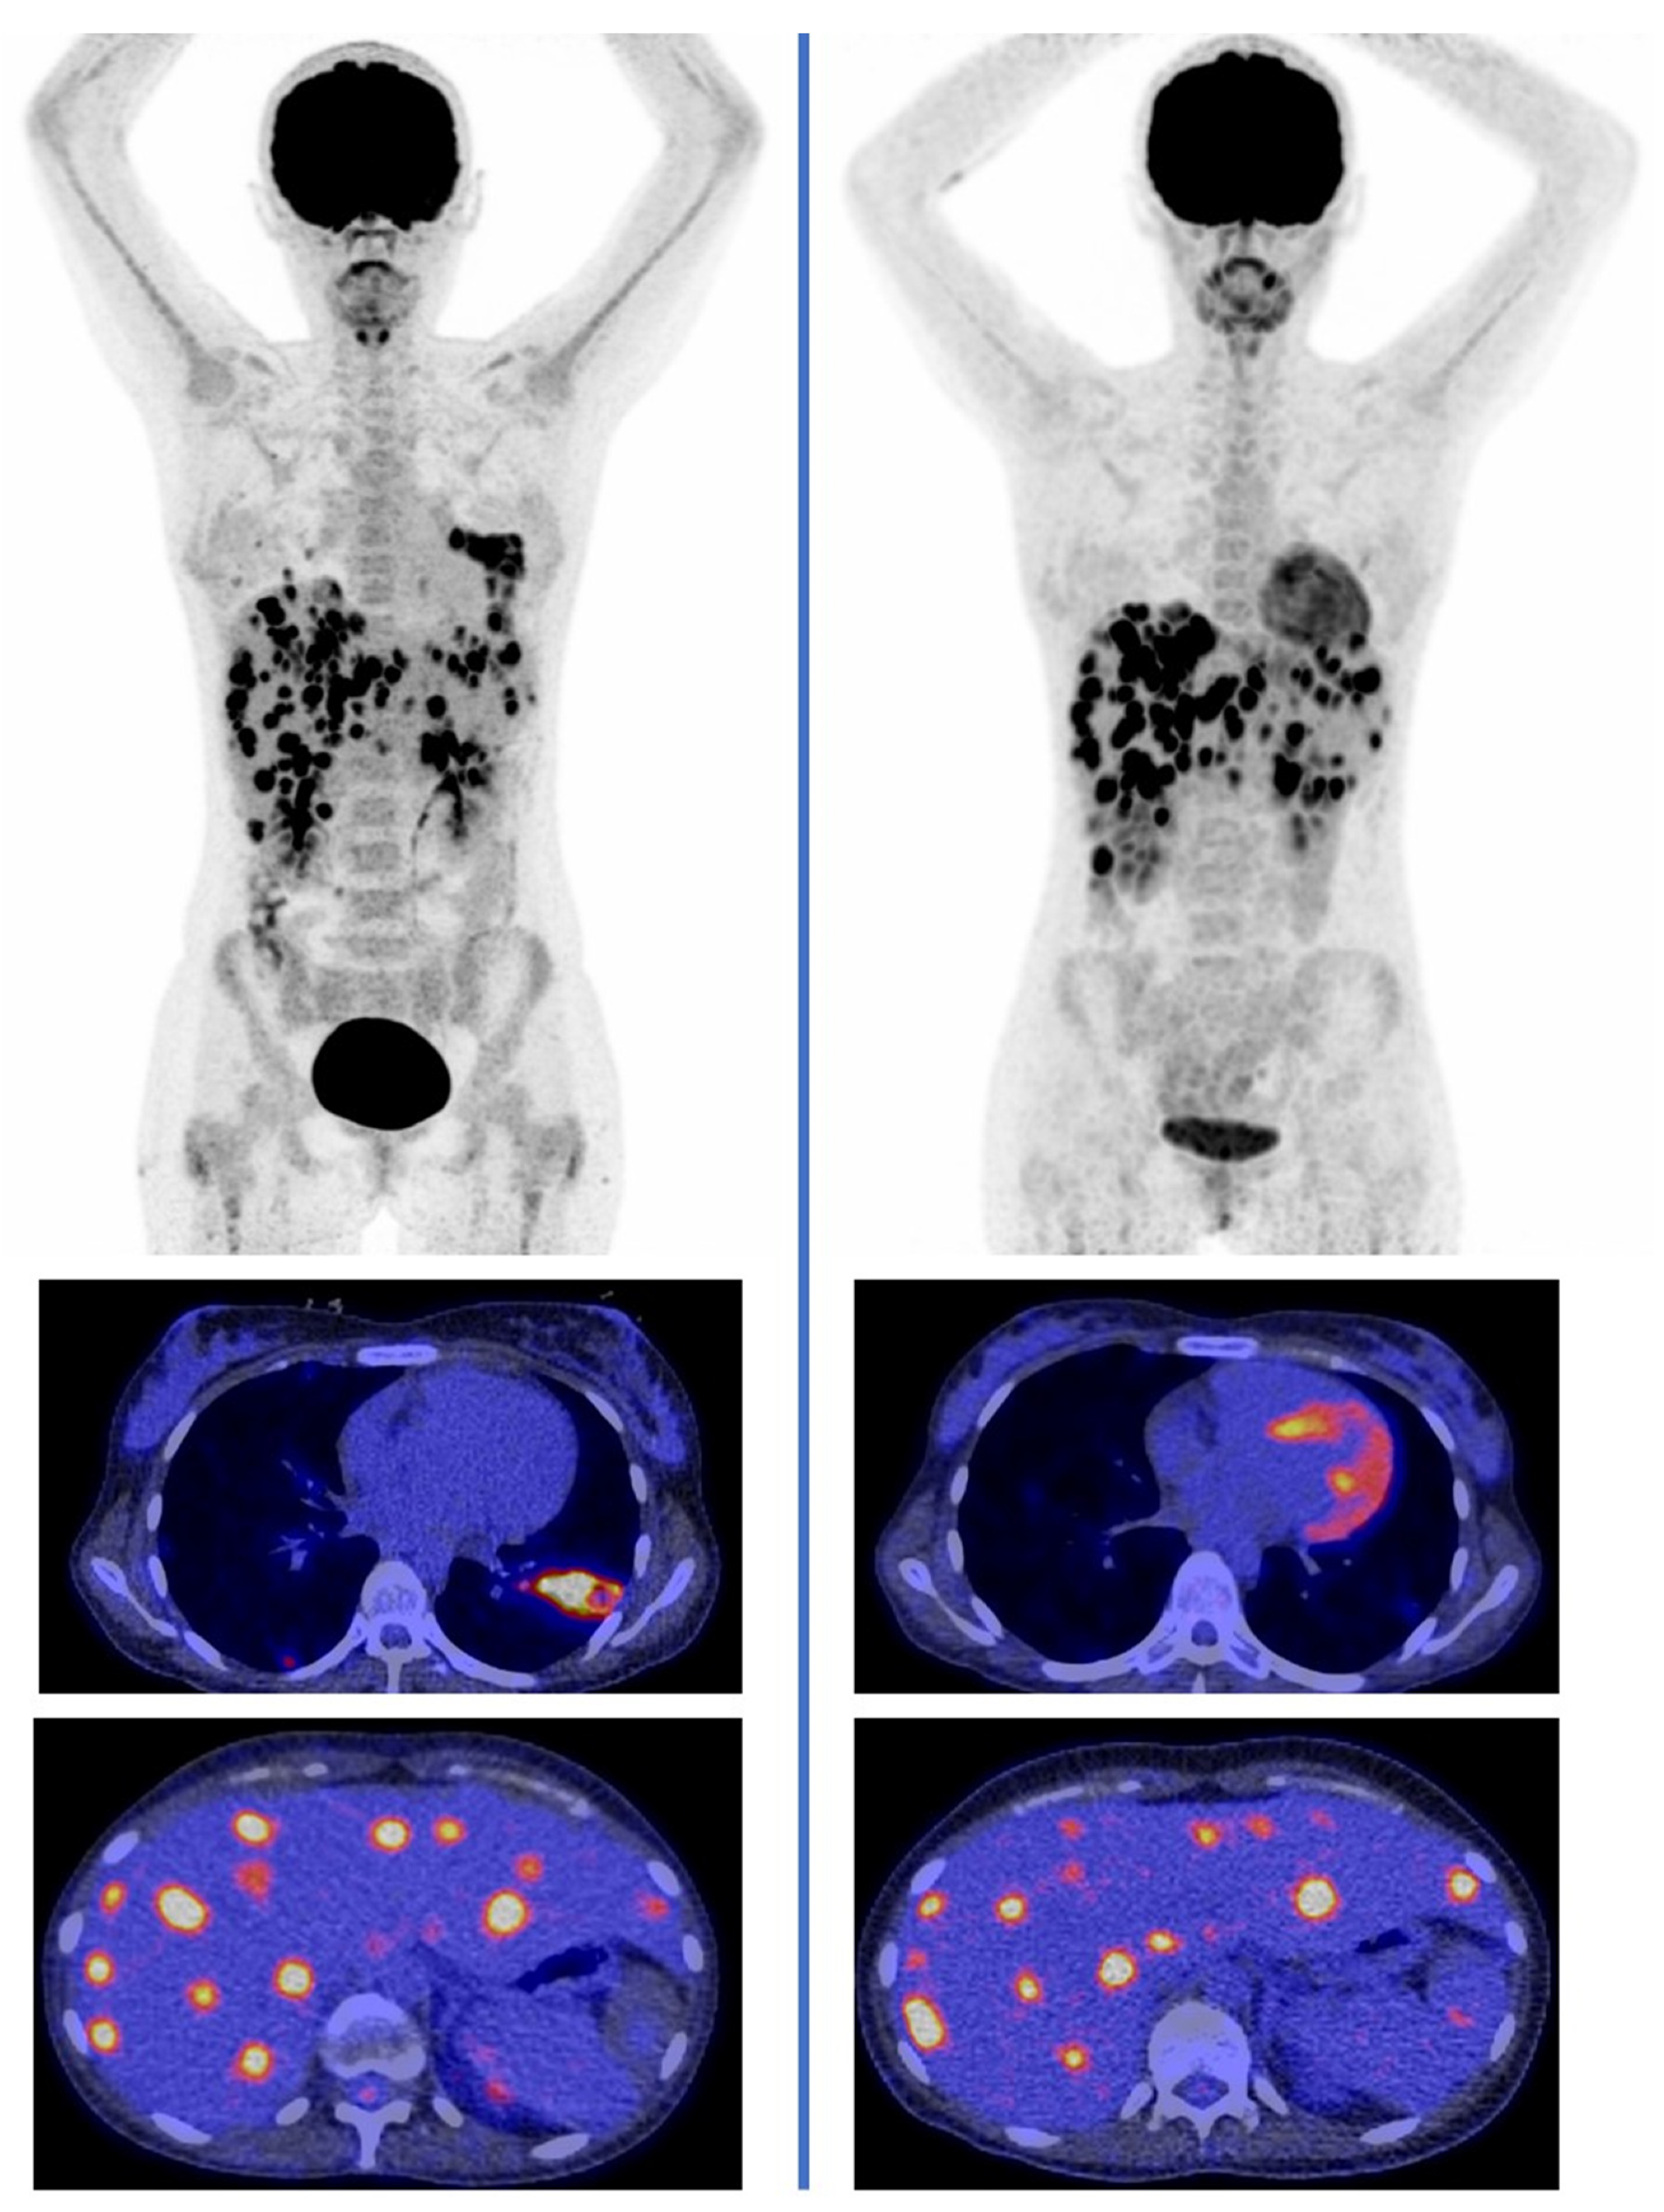

- Sharma, P.; Mukherjee, A.; Karunanithi, S.; Bal, C.; Kumar, R. Potential role of 18F-FDG PET/CT in patients with fungal infections. AJR Am. J. Roentgenol. 2014, 203, 180–189. [Google Scholar] [CrossRef]

- Hot, A.; Maunoury, C.; Poiree, S.; Lanternier, F.; Viard, J.P.; Loulergue, P.; Coignard, H.; Bougnoux, M.E.; Suarez, F.; Rubio, M.T.; et al. Diagnostic contribution of positron emission tomography with [18F]fluorodeoxyglucose for invasive fungal infections. Clin. Microbiol. Infect. 2011, 17, 409–417. [Google Scholar] [CrossRef]

- Ankrah, A.O.; Creemers-Schild, D.; de Keizer, B.; Klein, H.C.; Dierckx, R.A.J.O.; Kwee, T.C.; Span, L.F.R.; de Jong, P.A.; Glaudemans, A.W.J.M. The added value of [18F]FDG PET/CT in the management of invasive fungal infections. Diagnostics 2021, 11, 137. [Google Scholar] [CrossRef] [PubMed]

- Douglas, A.P.; Thursky, K.A.; Worth, L.J.; Drummond, E.; Hogg, A.; Hicks, R.J.; Slavin, M.A. FDG PET/CT imaging in detecting and guiding management of invasive fungal infections: A retrospective comparison to conventional CT imaging. Eur. J. Nucl. Med. Mol. Imaging 2019, 46, 166–173. [Google Scholar] [CrossRef]

- Leroy-Freschini, B.; Treglia, G.; Argemi, X.; Bund, C.; Kessler, R.; Herbrecht, R.; Imperiale, A. 18F-FDG PET/CT for invasive fungal infection in immunocompromised patients. QJM 2018, 111, 613–622. [Google Scholar] [CrossRef] [PubMed]

- Ankrah, A.O.; Span, L.F.R.; Klein, H.C.; de Jong, P.A.; Dierckx, R.A.J.O.; Kwee, T.C.; Sathekge, M.M.; Glaudemans, A.W.J.M. Role of FDG PET/CT in monitoring treatment response in patients with invasive fungal infections. Eur. J. Nucl. Med. Mol. Imaging 2019, 46, 174–183. [Google Scholar] [CrossRef]